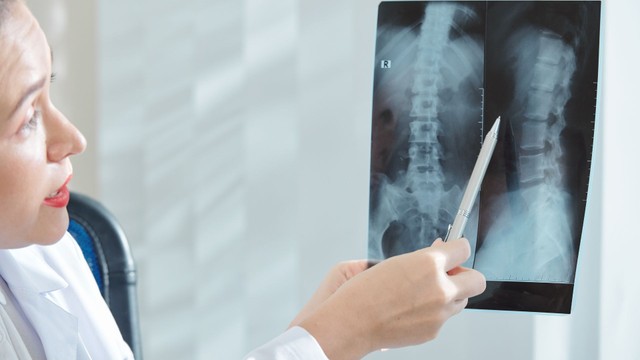

X quang